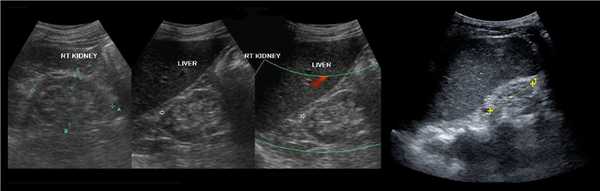

В положении пациента на спине по среднеключичной и переднеподмышечной линии выводим правую почку в соседстве с печенью, а левую почку вблизи селезенки. Оцените эхогенность почек. Корковый слой почки в норме изо- или гипоэхогенный по отношению к печени и гипоэхогенный по отношению к селезенке.

Рисунок. Эхогенность органов сравнивают на одном срезе. На УЗИ нормальная почка по соседству с печенью (1) и селезенкой (2). У детей до 6 месяцев паренхима почек в норме может быть гиперэхогенной по сравнению с печенью (3).

Рисунок. На УЗИ почечное ложе слева пустое (1). Обе почки расположены справа, срастаются полюсами (2, 3). Заключение: Аномалия взаиморасположения почек — I-образная удвоенная правая почка.